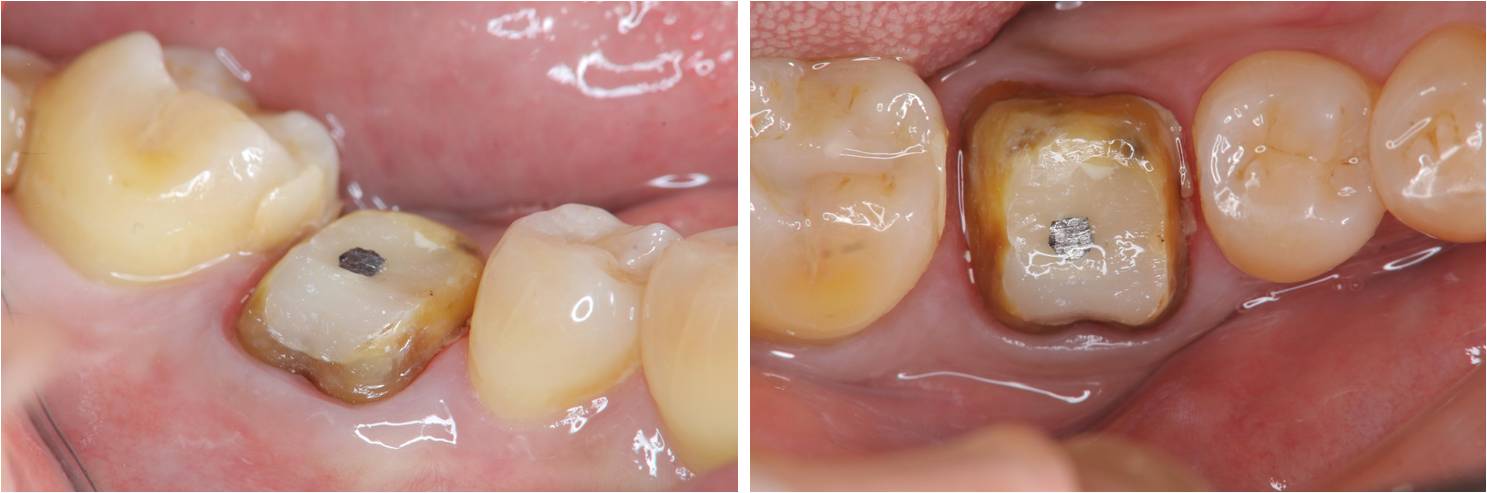

全瓷冠牙齒製備